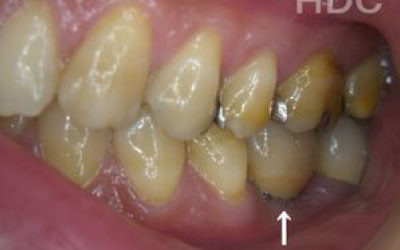

誰でも噛むときに歯に何十キロもの力がかかっています。当然、歯の本数が減れば減るほど残っている歯にかかる負担が大きくなります。

ブリッジ治療でも、 失った歯にかかっていた力は残っている前後の歯が支えます。 結果的に、残っている歯には抜歯していないときの1.5〜2倍程度の力がかかるのです。

入れ歯の場合は、バネをかけている歯や残っている歯への負担が大きくなります。多くの方が無意識で残っている歯で噛んでいることから、使う回数が極端に多くなったり過剰な力が加わり、結果的に折れるなど残っている歯の寿命を縮めます。

ただインプラントは、人工歯根を通して骨が力を支えるので、残っている歯への負担が圧倒的に少ないのです。

ブリッジなどの治療では前後の歯を大きく削る必要があります。場合によっては、虫歯でもないのに歯の神経をとることも。実は神経をとって被せ物をすると、歯は一気に最終ステージになってしまいます。

しかしインプラント治療なら、前後の歯を削る必要も神経をとる必要もありません。歯の寿命を延ばす上でも、健康な歯をできるだけ削らないのはとても大切なことなのです。

インプラントは、入れ歯のように取り外す手間がなく、自分の歯のような感覚でしっかり噛めるのが大きな魅力です。

中でも最も大きな利点は、まわりの歯に余計な負担をかけないという点です。

ブリッジや入れ歯は、周囲の健康な歯に力の負担をかけてしまうため、それらの歯が次々に弱って抜けてしまうことも少なくありません。

それに対しインプラントは独立して支える構造のため、他の歯を守ることができる、歯にやさしい治療法なのです。